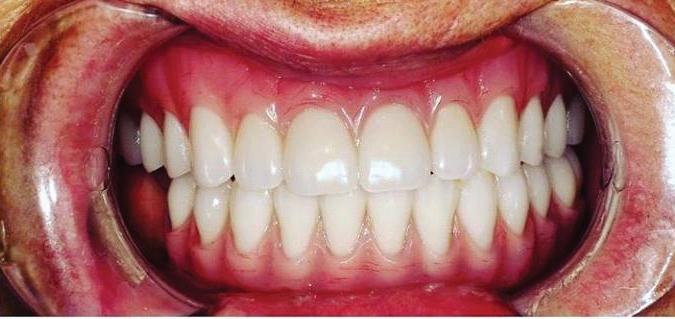

Submitted By Sivakumar Sreenivasan, DMD, MDS

Dental Implant Center of Rockville

Can just four implants replace all of the teeth on the top or the bottom of your mouth? Thanks to advances in dental implant technology, that answer is a resounding yes.

Believe it or not, tooth loss is extremely common among adults, especially as we age. In fact, more than 35 million people in America are missing all of their upper and/or lower teeth. Rather than living with the discomfort and hassles of dentures, many people are opting for what is called “all-onfour” dental implant restoration.

All-On-Four: One Full Arch Of Teeth, Four Dental Implants

Here’s where it gets really interesting: You do not need a dental implant for each and every one of your missing teeth. All you need is four precisely placed implants on the top of your mouth, and four on the bottom, to restore your full smile. That’s the beauty of the all-on-four. And because the implant is made of titanium, it has the unique ability to fuse to living bone and function as part of it. So eventually, the dental implant becomes part of the jawbone and serves as a strong, long-lasting foundation for your new teeth.

this bone fusion has another important benefit: it prevents future bone loss in the jaw. This helps to maintain a more youthful facial structure – and better oral health. But perhaps the biggest surprise about the all-on-four is how quickly it can transform your life.